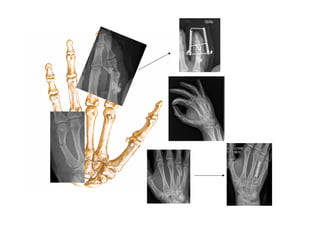

8.1 Fracturas de dedos

Fract. falanges distales (50%)

-Drenaje del hematoma

subungueal

-Férula de STAC

Fract. Falanges proximal y media Fracturas extraarticulares:

-No desplazadas: sindactilia

-Desplazadas: reducción cerrada /

reducción abierta

Fracturas intraarticulares:

-No desplazadas: movilización precoz.

-Desplazadas: quirúrgico

Alineación no

aceptable:

-Angulación >10º

-Acortamiento

>5mm

-Contacto<50%

-Malrotación

Fracturas de metacarpianos

No desplazadas: Férula de yeso y

citar en una semana en CEX

Traumatología.

Desplazadas: reducción cerrada +

férula

Luxaciones dedos Reducción mecanismo

inverso + sindactilia